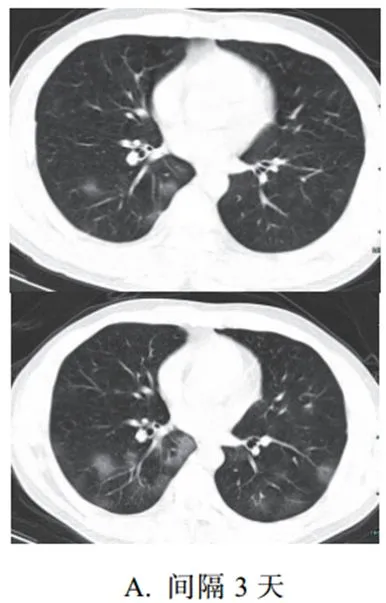

二、进展期征象

新冠肺炎大多数病例进展迅速,复查 CT 影像发生明显变化

表现为病灶数目明显增多,范围明显扩大,密度增高,病灶分布由外周向中央推进

根据既往 SARS 病理学机制,提示为肺泡腔内聚集大量细胞渗出液、间质内血管扩张渗出;肺泡连通起来形成融合态势(图 2-11)

图 2-11 病灶数目增多、范围扩大 (A-D)